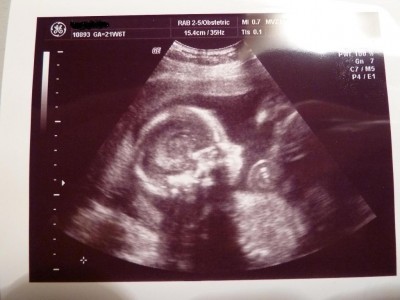

@all: heute hatte ich wieder VU. War heute recht angenehm bei meiner FA. Der kleine Mann ist jetzt schon 28 cm lang und wiegt ca. 550 g. heute gab es überraschenderweise mal ein schönes Profilbild, dass ich euch gleich mal mir einstelle. Ich bin total verliebt in den kleinen Schatz…guckt euch mal das niedliche Profil an…